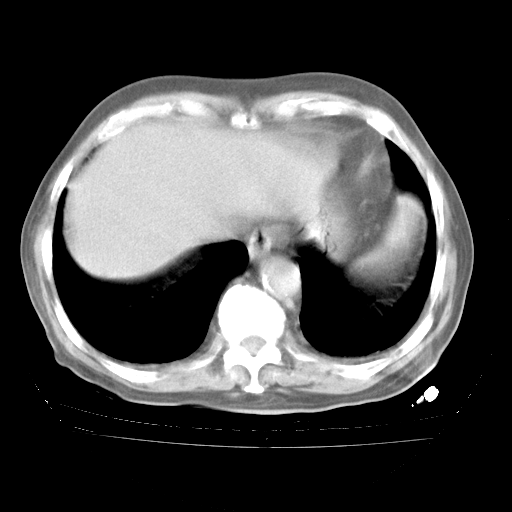

4月28日肺部CT——再次出现类似去年5月9日——透光度降低,“间质性”改变。

个人阅读4.14日肺部CT平扫:纵隔窗无异常,但肺窗示:双下肺内、后基底段有片絮状侵润影,部位以后基底段为著,以间质改变为主,呈急性肺泡炎征像,和首次住院影像学有相似之处。仅是个人读片,明日请相关专家再读片哈。其它建议同上。

今请临免主任会诊后认为:4月14日胸部CT已有双下肺间质性改变。患者病情复发多系激素减量过快不正规所致。目前甲强龙80mg/日,一周后酌情开始减量,不易过快。环磷酰胺若已停用,暂不使用。他同意目前抗菌药物使用,但应考虑是否加用B-内酰胺类抗菌药物(中性细胞明显增高);2、结核复发目前依据不足;3、若免疫全套各项指标正常,考虑多系特发性肺间质炎可能大。4、加强支持,并注意保护胃黏膜。